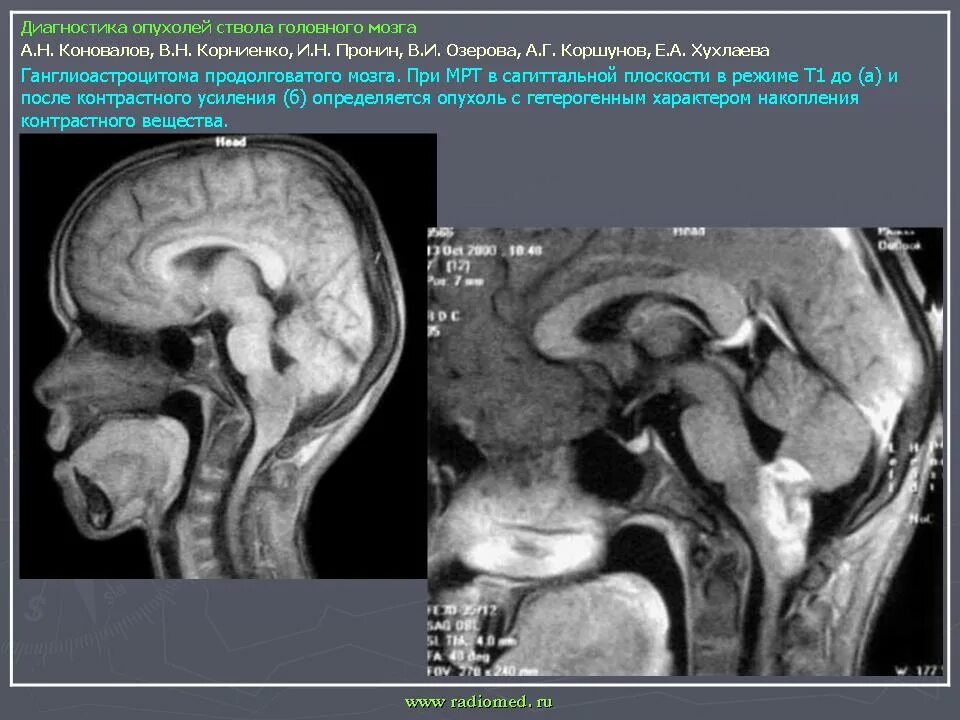

Сколько живут с доброкачественной опухолью головного мозга